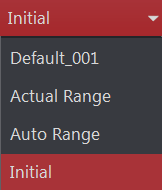

Az eRAD PACS támogatja az ablak szélességének és közepének előzetes beállításait. Az előzetes beállítások lehetővé teszik egy vagy több beállítás csoportosítását egy specifikus funkcióra. Ezután ezek a beállítások használhatók, ha kiválasztja őket a listából. Előre beállított ablak és szint esetén létrehozhat modalitás-specifikus ablak-/szintpárokat, és alkalmazhatja azokat a jelenlegi képhez úgy, hogy kiválasztja a címkét a listából. Az ablakok és szintértékek előre beállított listája nyilvántartja az összes mentett ablakolási beállítást egy specifikus modalitás típushoz. Az előre beállított ablakolási lista az Ablakolás eszköztárban jelenik meg. Az előre beállított értékek listája a legördíthető menüben található. Néhány alapértelmezett érték megtalálható az alapértelmezett ablakolási listában.

Az előre meghatározott beállítások az Ablakolás eszköztár Ablakolás lenyíló menüjében érhetők el a kiválasztott képhez.

Beállítások |

Leírás |

Tényleges tartomány |

A teljes képernyős szélességre vonatkozik, a maximális tartomány közepén központosítva, a kódolt képinformációval definiálva |

Automatikus ablakolási tartomány |

Az adatokon végzett hisztogram-kiegyenlítési elemzésre vonatkozik. A legtöbb esetben ennek eredménye egy kisebb eltérés a valós tartománytól a pixeladatok értékekké konvertálása miatt |

Kezdeti |

Az alapértelmezett, képobjektumban kifejezetten meghatározott ablakszélesség és középpont értékek |

Megjegyzés: A Kezdeti, Tényleges tartomány és Automatikus tartomány beállítások nem törölhetők vagy módosíthatók.